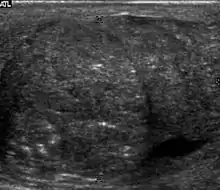

Epididymo-orchitis in a 77-year-old man. (a) Transverse sonography shows enlargement of the epididymis with hypoechogenicity noted over the testis and epididymis associated with scrotal wall thickening. (b) Color Doppler sonography showed hyperemic change of the testis and epididymis, presenting as an “inferno” vascular flow pattern.

Epididymitis and epididymo-orchitis are common causes of acute scrotal pain in adolescent boys and adults. At physical examination, they usually are palpable as tender and enlarged structures. Clinically, this disease can be differentiated from torsion of the spermatic cord by elevation of the testes above the pubic symphysis. If scrotal pain decreases, it is more likely to be due to epidiymitis rather than torsion (Prehn's sign). Most cases of epididymitis are secondary to sexually transmitted disease or retrograde bacteria infection from the urinary bladder.[4] The infection usually begins in the epididymal tail and spreads to the epididymal body and head. Approximately 20% to 40% of cases are associated with orchitis due to direct spread of infection into the testis.

At ultrasound, the findings of acute epididymitis include an enlarged hypoechoic or hyperechoic (presumably secondary to hemorrhage) epididymis [Fig. 20a]. Other signs of inflammation such as increased vascularity, reactive hydrocele, pyocele and scrotal wall thickening may also be present. Testicular involvement is confirmed by the presence of testicular enlargement and an inhomogeneous echotexture. Hypervascularity on color Doppler images [Fig. 20b] is a well-established diagnostic criterion and may be the only imaging finding of epididymo-orchitis in some men.